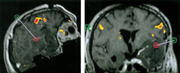

fMRI/PET: Auch die Integration funktioneller Bilddaten ist möglich. Hierzu wird parallel zum

fMRI-Volumendatensatz ein T1-gewichteter 3D-Datensatz mit den funktionellen Daten präoperativ erhoben.

Dieser kann ebenfalls semiautomatisch mit hoher Genauigkeit mit dem interventionellen Datensatz koregistriert

werden. Als Visualisierungsmethoden werden ähnliche Methoden verwendet, wie für die CT-Daten.